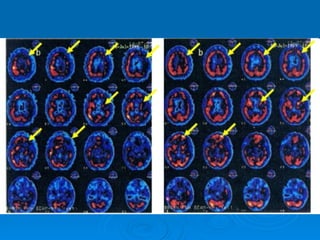

Wat zijn de gevolgen Afhankelijk van: plaats in hersenen hoeveelheid weefsel

Linker hersenhelft krachtsverlies rechts uitval gezichtsveld rechterkant ogen taal en spreken moeilijk langzaam, onzeker gedrag Rechter hersenhelft krachtsverlies links uitval gezichtsveld linkerkant ogen niet reageren op alles van links problemen met ruimtelijke waarneming  overschatten

Linker hersenhelft krachtsverliesrechts uitval gezichtsveld rechterkant ogen taal en spreken moeilijk langzaam, onzeker gedrag Rechter hersenhelft krachtsverlies links uitval gezichtsveld linkerkant ogen niet reageren op alles van links problemen met ruimtelijke waarneming overschatten